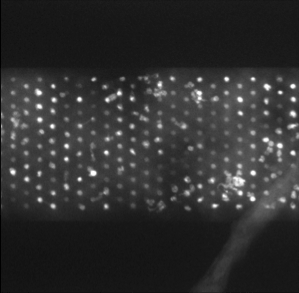

5.5 Electron microscopy cell images with nonuniform background

In this subsection we show that our multiscale segmentation approach can also be used for real-world images where the background is less homogenous as in the cell images before. In Figure 15 (a) we show an electron microcopy dataset of acinar cells provided by [Rie]. For a more obvious visual interpretation we reverted the contrast from the original EM dataset (bright background with dark cells) to a dark, but not uniform, background with brighter cells. The intensity of the cells is also inhomogeneous and varies from very bright cells (left) to cells with an intensity closer to the background (right). Figure 15 (b) shows the color-coded spectral response function and (c) the color-coded segmentation of the cells. We see that the inhomogeneous intensity of the cells is reflected in the scales found by our method. The inhomogeneity of the background is not influencing the segmentation result and the constants and can still be estimated beforehand from the data without further adaption. One problem that occurs is the ambiguity of size and intensity scales which can be observed when comparing small but bright cells on the right (visualized in light green) with larger cell clusters on the right (also visualized in light green). Currently our method is not able to differentiate their scales. A useful extension of our method would be a combination of our multiscale approach with a watershed type algorithm that is able to split cell clusters into individual cells of different scales.